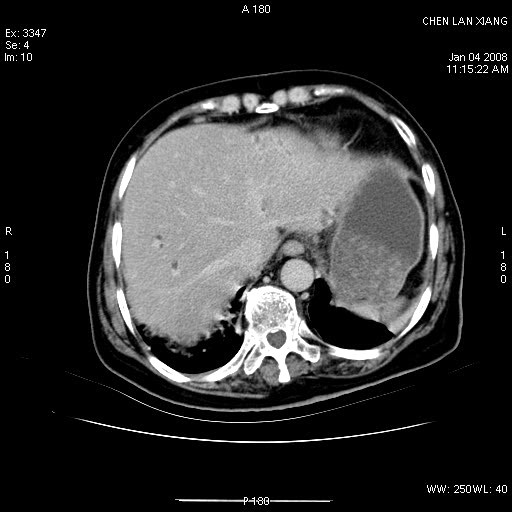

女,76岁,腹痛3-4天,b超示:肝内实性肿物,胆囊强回声,胆总管扩张.

考虑:1、胆总管下端结石伴梗阻性肝内外胆管扩张(肝左叶外侧段肝内胆管多发结石、胆管炎);

2、肿囊癌累及肝,不除外 黄色肉芽肿性胆囊炎。

1 胆总管末端结石伴肝内胆管结石,肝内外胆管扩张。2 胆囊扩大,胆囊壁不规则增厚,内见软组织密度影。考虑:慢性胆囊炎,不除外胆囊癌!

ct所见:1、 肝内胆管结石,肝内外胆管扩张。低位胆道梗阻,胆总管下端结石;2 胆囊扩大,胆囊壁不规则增厚

考虑:胆总管下端结石并肝内外胆管扩张,肝内胆管结石;

标题: 肝右叶病灶

胆囊癌侵犯肝右叶?

1)胆囊癌伴肝脏转移。2)胆总管下端结石、肝内胆管结石伴肝内外胆管扩张。